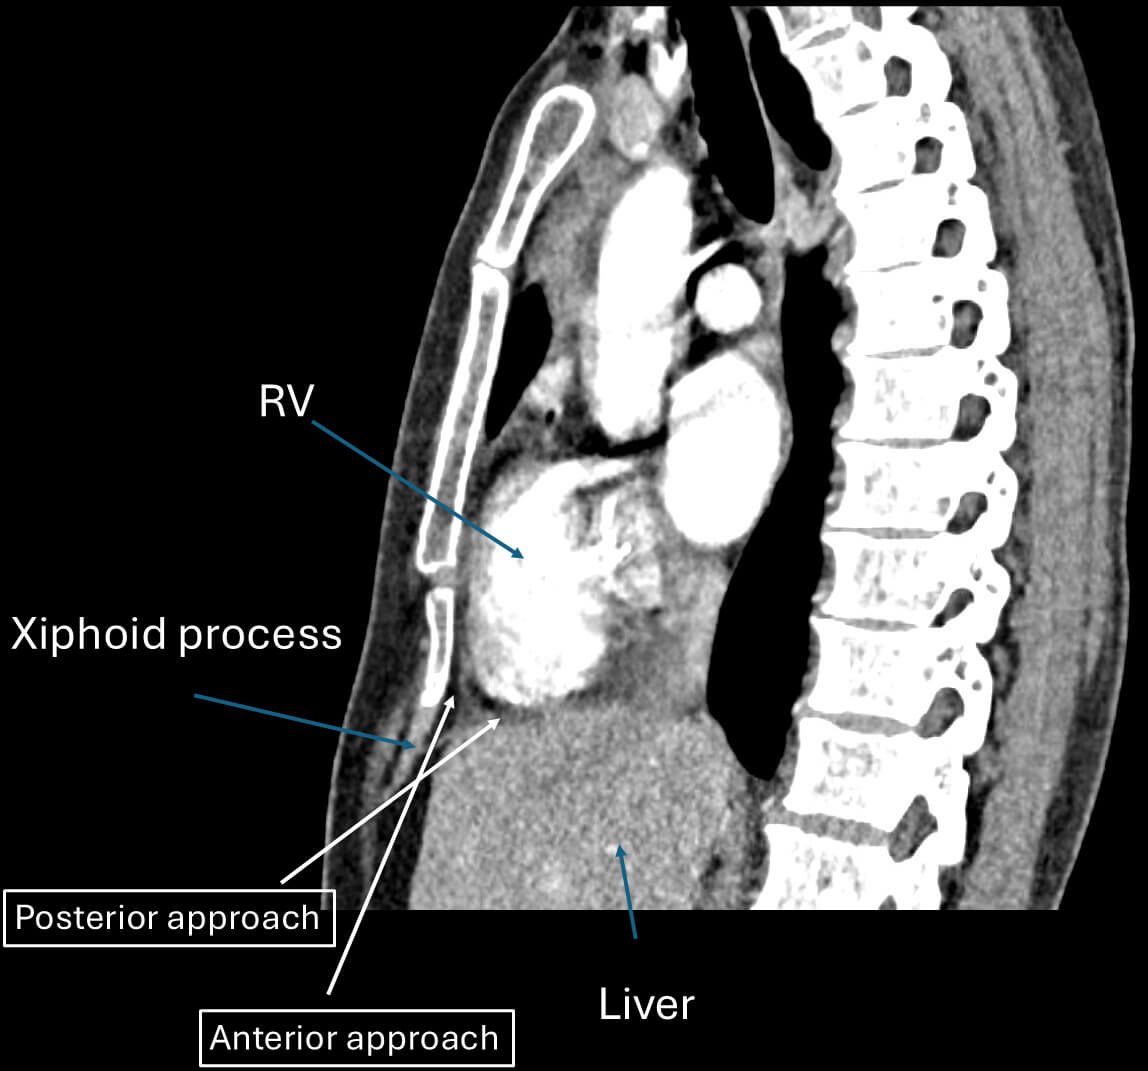

The anterior approach is the most commonly used technique in contemporary practice. In this method, the needle is advanced in a relatively anterior direction, typically aimed toward the left shoulder. Under fluoroscopic guidance, the needle is introduced at a shallow angle relative to the skin. This trajectory generally allows entry into the pericardial space just anterior to the RV. The anterior approach is often preferred in patients with normal or mildly rotated cardiac anatomy, as it facilitates more direct access to the anterior, lateral, and apical surfaces of the left ventricle.

In contrast, the posterior approach employs a steeper needle trajectory directed inferiorly and posteriorly toward the diaphragmatic surface of the heart. This path typically advances the needle deeper into the abdomen, passing posterior to the liver and occasionally in proximity to bowel loops, before reaching the pericardial space.

The most important difference between these two approaches lies in their complication profiles. With the anterior approach, the primary risks include inadvertent RV puncture, given the proximity of the entry site to the RV surface, as well as injury to the left internal mammary artery (LIMA) if the needle trajectory passes too close to the sternum.

On the other hand, the posterior approach carries a higher risk of serious non-cardiac complications. As the needle passes through the diaphragm and into the abdominal cavity, it is in close proximity to vital organs, including the liver, bowel, colon, and inferior epigastric arteries. Case series and retrospective analyses have identified hepatic laceration, intra-abdominal hemorrhage, and bowel perforation. These might be potentially life-threatening complications, especially when hypotension occurs during the procedure without evidence of cardiac tamponade. While the posterior approach can be effective in specific scenarios, such as when the anterior space is obliterated due to adhesions from prior open-heart surgery [10], it is generally considered less favorable in routine practice due to its higher risk profile [11]. Although rare, when epicardial ablation needs to be considered as an approach to access the epicardial substrate for atrial fibrillation, a posterior approach is required to reach the posterior left atrium and roof, where additional ablation is typically needed [12]. Fig. 3 demonstrates the difference in angle and entry for both anterior and posterior approaches. Typically, skin entry is lower in the anterior approach as opposed to the posterior approach, which requires the needle angle to be adjusted to be shallower.

Fig. 3.

Anterior and posterior approach. This figure demonstrates the difference in angle and entry for both anterior and posterior approaches. Typically, skin entry is lower in the anterior approach as opposed to the posterior approach. RV, right ventricle.